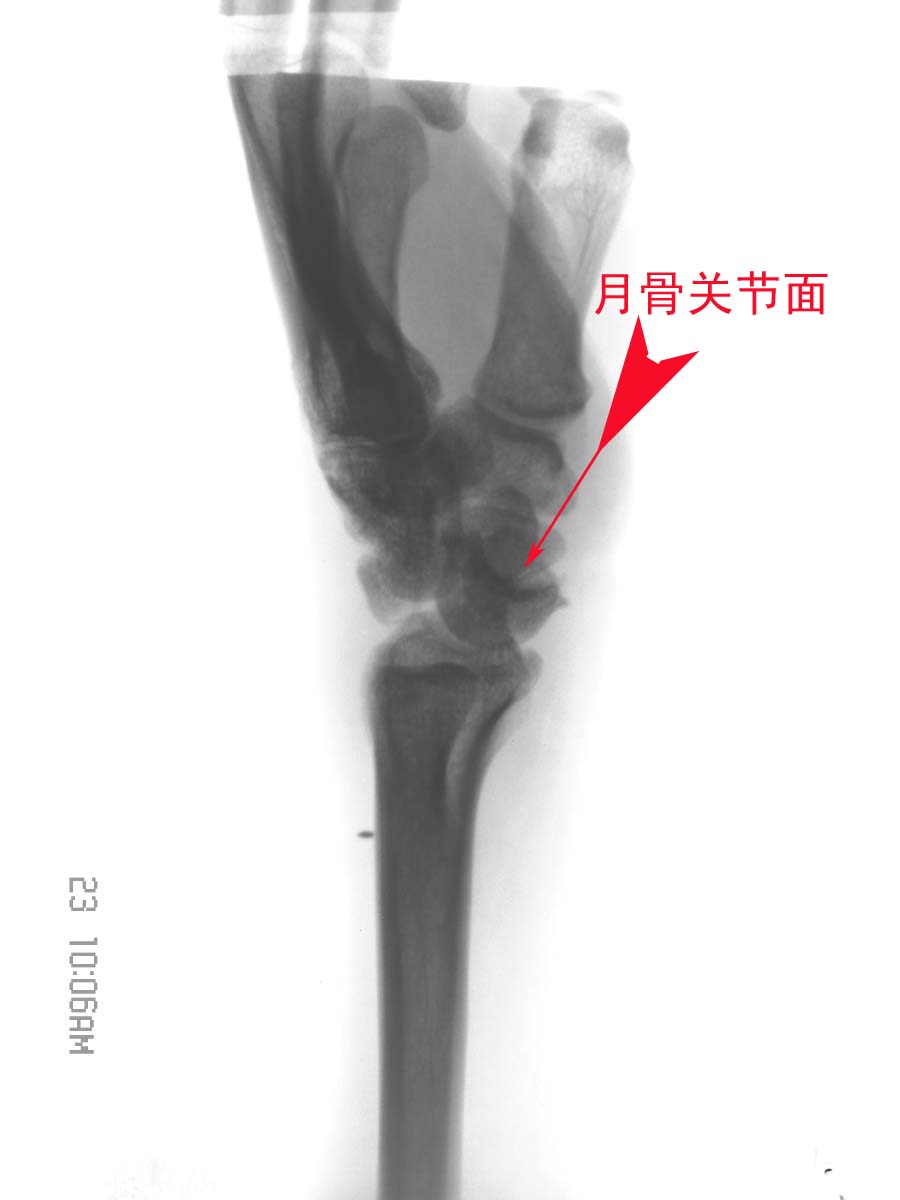

男,36岁,外伤后左腕部肿痛2小时。

左舟骨骨折伴有左月骨半脱位。

月骨于正位片上为楔形、侧位片上为月牙形,窝状关节面朝前、且与头状骨紧贴。

1).月骨脱位:正位片示月骨由四边形便成三角形或橘瓣状,并向尺侧移位。侧位月骨前移、旋转,窝状关节前空虚。

此例我感觉是“经舟骨月骨周围脱位”,我曾发布过一例,如下图:

下面一例“月骨脱位病例”,请大家比较一下:

我赞同是1、“经舟骨月骨周围脱位”,表现为月骨周围脱位拌舟骨骨折,且骨折远段随头骨向后脱位,而骨折近段与桡骨、月骨关系保持正常。2、软组织内金属异物。